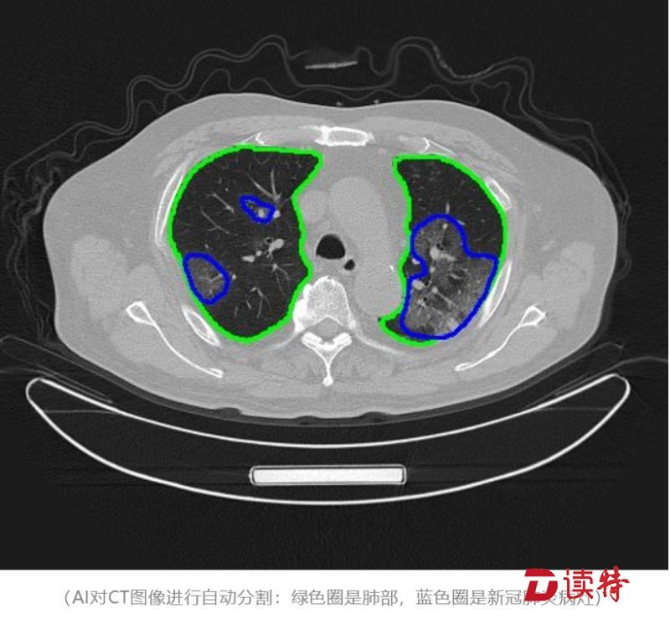

“腾讯觅影”AI辅助诊断

疫情伊始,云天励飞研发的人工智能红外测温设备及系统,可以快速识别发热患者,有效提高检测效率,在国务院联防联控机制新闻发布会上被点名表扬;腾讯用“腾讯觅影”AI辅助医生提高CT检查效率;普渡科技提供 “欢乐送”智能配送机器人,负责服务台问询、导诊、送餐等任务,甚至医院里高风险的消杀工作;大疆无人机协助交警开展执勤管控。